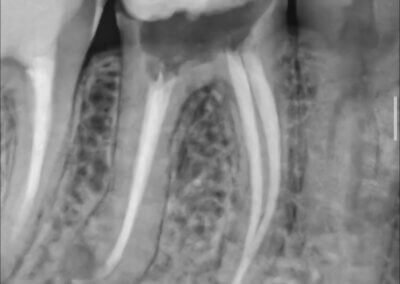

Endodonția este o ramură esențială a stomatologiei, axată pe diagnosticarea, prevenirea și tratamentul afecțiunilor pulpei dentare și a țesuturilor periapicale. Această specialitate joacă un rol crucial în salvarea dinților naturali, evitând extracțiile și menținând sănătatea orală pe termen lung. Prin tehnici avansate și echipamente de ultimă generație, endodonția asigură tratamente precise și eficiente, contribuind la redarea sănătății și funcționalității dinților într-un mod durabil și predictibil.